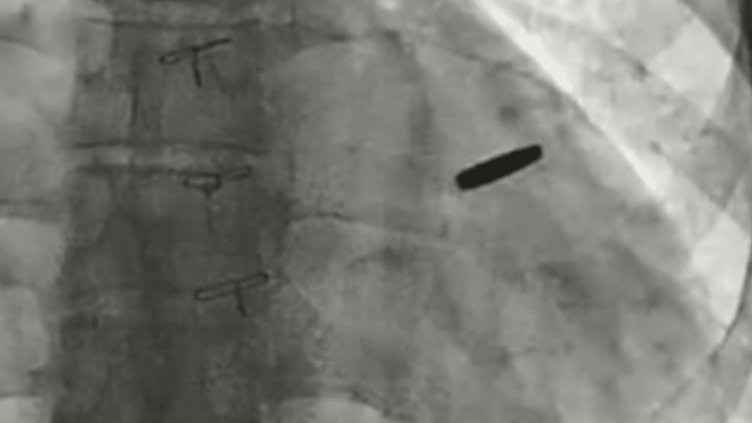

Украински лекари са извадили куршум, заседнал в сърцето на войник, защитавал стоманодобивния завод „Азовстал“ в Мариупол и оцелял три години в руски плен, според Борис Тодуров, директор на Украинския институт по сърдечни заболявания, на 19 септември.

Тодуров каза, че куршумът по чудо е пропуснал жизненоважни структури, което е позволило на боеца да живее с него, забит в сърцето му, в продължение на три години.

„Куршумът вече е изваден. Човекът е имал късмет. Мисля, че ще живее дълъг и щастлив живот“, каза Тодуров, държейки куршума по време на брифинг за пресата.

Лекарите казаха, че куршумът не е причинил сериозни щети през годините, в които е останал заседнал в сърцето.